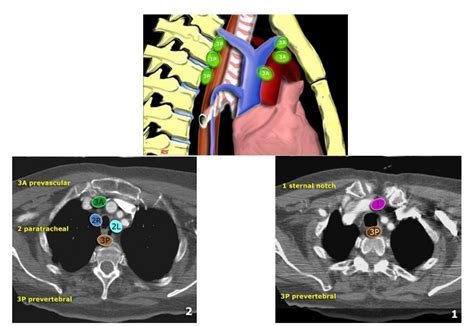

EBUS is primarily utilized for the diagnosis and staging of lung cancer, particularly for assessing mediastinal and hilar lymph nodes. The procedure involves the insertion of a flexible bronchoscope, equipped with an ultrasound probe at its tip, through the mouth or nose into the lungs. This allows for the examination of the airway walls and parabronchial structures. The ultrasound component provides high-resolution images that help in identifying abnormalities, such as enlarged lymph nodes, which can then be sampled for cytological examination using fine-needle aspiration (FNA) under real-time ultrasound guidance.

The technical specifications of EBUS equipment include high-frequency ultrasound probes that operate within the range of 5-12 MHz, providing detailed images of the structures surrounding the airways. The procedure is typically performed under conscious sedation or general anesthesia, ensuring patient comfort. During the procedure, the physician navigates the bronchoscope to the target area, uses the ultrasound to locate the lymph nodes or lesions of interest, and then performs FNA to collect tissue samples for pathological examination. The samples are then analyzed to determine the presence of cancer cells, which aids in diagnosing and staging the disease.